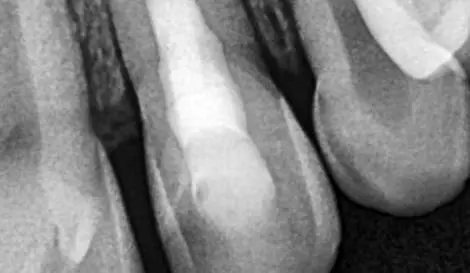

Діагностика і лікувальна тактика: коли можна не втручатись в пульпу, коли можна видаляти її частково і що робити, коли пільпа загинула. Часткова і повна пульпотомія: коли і як це робити? Що робити коли пульпа загинула повністю? Апексифікація і апексогенез, гідроксид кальцію і пробка з МТА. Останні регенераторні тенденції в ендодонтії. Реваскуляризація - що це і коли варто робити?